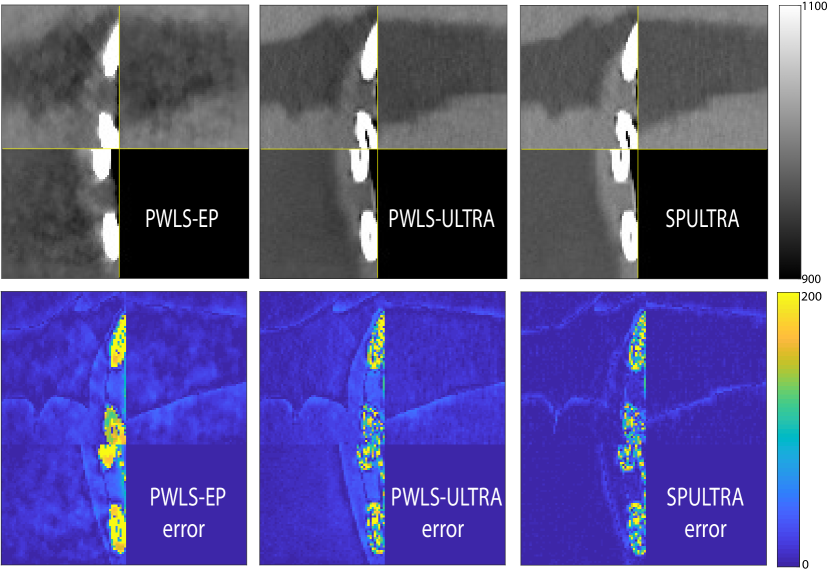

V-B2 Reconstruction results for the synthesized clinical data

Fig. 9 shows three axial slices from the 3D reconstructions with SPULTRA and PWLS-ULTRA at : the middle slice (No. 67) and two slices located farther away from the center (No. 90 and No. 120). The image profiles along a horizontal line (shown in green) in the displayed slices are also shown in Fig. 9. The reconstructed slices using PWLS-ULTRA appear darker around the center compared to the “true” clinical image and the reconstructions with SPULTRA. This means PWLS-ULTRA produces a strong bias in the reconstruction. The bias can be observed more clearly in the profile plots: the pixel intensities for the SPULTRA reconstruction better follow those of the “true” clinical image, while those for the PWLS-ULTRA reconstruction are much worse than the “true” values. Moreover, SPULTRA achieves sharper rising and failing edges compared to PWLS-ULTRA. In other words, SPULTRA also achieves better resolution than PWLS-ULTRA. Fig. 9 also shows a zoomed-in ROI for each of the chosen slices, and highlights some small details with arrows. It is clear that in addition to reducing the bias, SPULTRA reconstructs image details better than PWLS-ULTRA.

V-C2 Results

Fig. 10 shows the reconstructions for the scan (reference image) along with the reconstructions for the simulated ultra low-dose scan obtained with PWLS-EP, WavResNet, PWLS-ULTRA, and SPULTRA. Visually, WavResNet fails to reconstruct the image but improves over the initial PWLS-EP reconstruction, while PWLS-ULTRA and SPULTRA provide better image quality. This indicates that the ULTRA-based methods may have a better generalization property than WavResNet, since they learn more fundamental features of CT images (also see [38]). We selected three smooth ROIs, where the pixel values are approximately constant. Tab. V(b) shows the mean and the standard deviation of pixel values for these ROIs for various methods and the standard-dose reference. Since the iterative RNN version of WavResNet only has small improvements over PWLS-EP, the pixel values do not change much compared with PWLS-EP. PWLS-ULTRA however reduces the bias in the central region of the image (ROI 2), but fails to correct the bias in the regions near the bones (ROI 1 and ROI 3). SPULTRA reduces the bias in the central region of the image, and also significantly corrects the bias near the bone regions. The standard deviations of the ROIs reconstructed by SPULTRA are comparable to those reconstructed by PWLS-ULTRA, and are close to those of the reference ROIs. Additionally, SPULTRA reconstructs the bone (indicated by the magenta arrow in the last two subfigures of Fig. 10) better than PWLS-ULTRA.